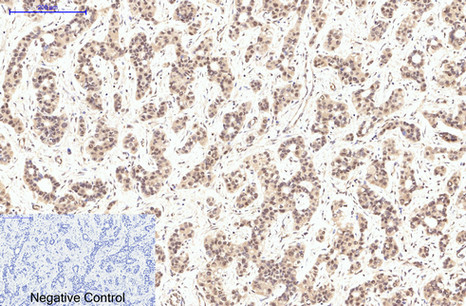

ARG66176 anti-eIF4A1 antibody IHC-P image

Immunohistochemistry: Paraffin-embedded Human liver cancer tissue stained with ARG66176 anti-eIF4A1 antibody at 1:200 dilution (4°C, overnight). Antigen Retrieval: Boil tissue section in Sodium citrate buffer (pH 6.0) for 20 min.

Negative control was used by secondary antibody only.